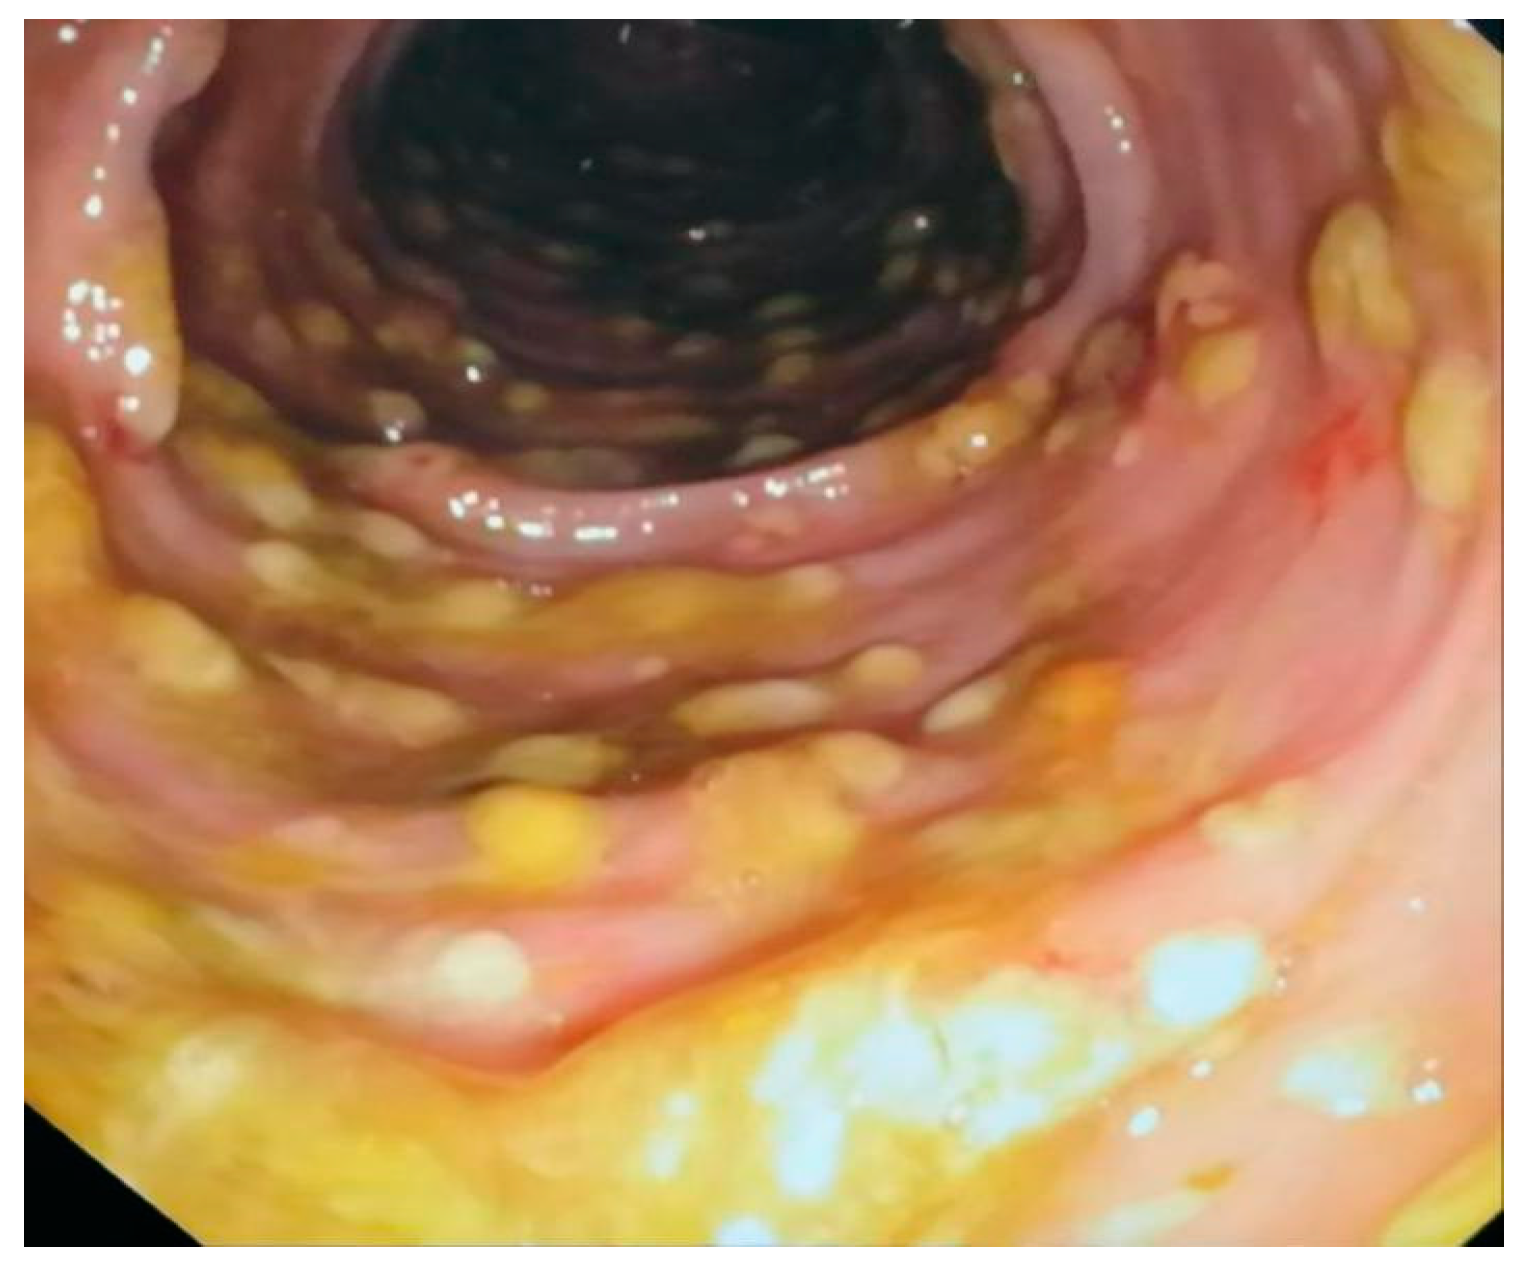

Fecal matter transfer technique involved dissolving 50 g of donated feces (less than 6 h after defecation) in 500 mL of saline 0.9%, mixing to obtain a homogeneous solution, and filtering. Immediately after, a total colonoscopy was performed with terminal ileoscopy, without sedation, in order to preserve anal sphincter control. The suspension, in its fresh state, was introduced from the terminal ileum, with 2/3 of the suspension in the right colon and the rest in the other segments of the colon at withdrawal. Endoscopic appearance of the colon before fecal microbiota transplant was performed, a typical endoscopic appearance of pseudomembranous colitis was outlined at colonoscopy at the moment of the FMT, despite antibiotic treatment. The colonic mucosa presented erased luster, erased vascularization, granular mucosa, and yellow-green pseudomembranous deposits. Classification of pseudomembranous lesions can be made based on the degree and depth of inflammatory changes, with grading of lesions from type 1 (“summit lesions”, focal surface epithelial inflammation or necrosis) (Figure 1 and Figure 2) to type 3 (mucosal necrosis and significant inflammatory debris) [38].

Figure 1.

Endoscopic picture before FMT, personal collection.